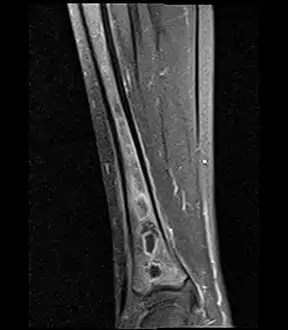

Coronal fat suppressed STIR image showing, bone marrow and subcutaneous edema as well as subperiosteal edema. The thin hypointense rim surrounding the intramedullary collection represents the reactive interface between the abscess and the body's attempt to wall it off. Coronal fat suppressed STIR image showing, bone marrow and subcutaneous edema as well as subperiosteal edema. The thin hypointense rim surrounding the intramedullary collection represents the reactive interface between the abscess and the body's attempt to wall it off.